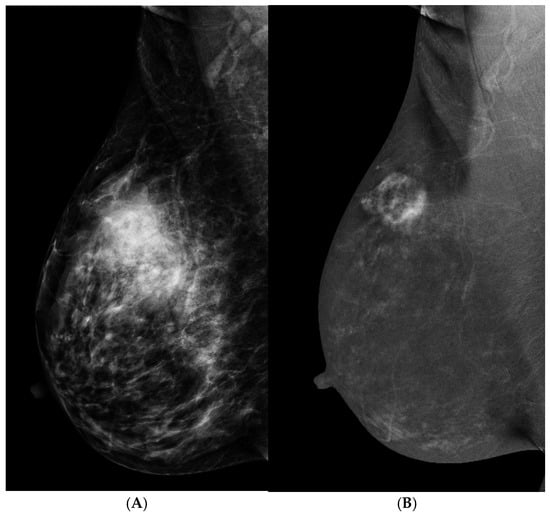

3.1. Problem Solving

3.2. Palpable Mass